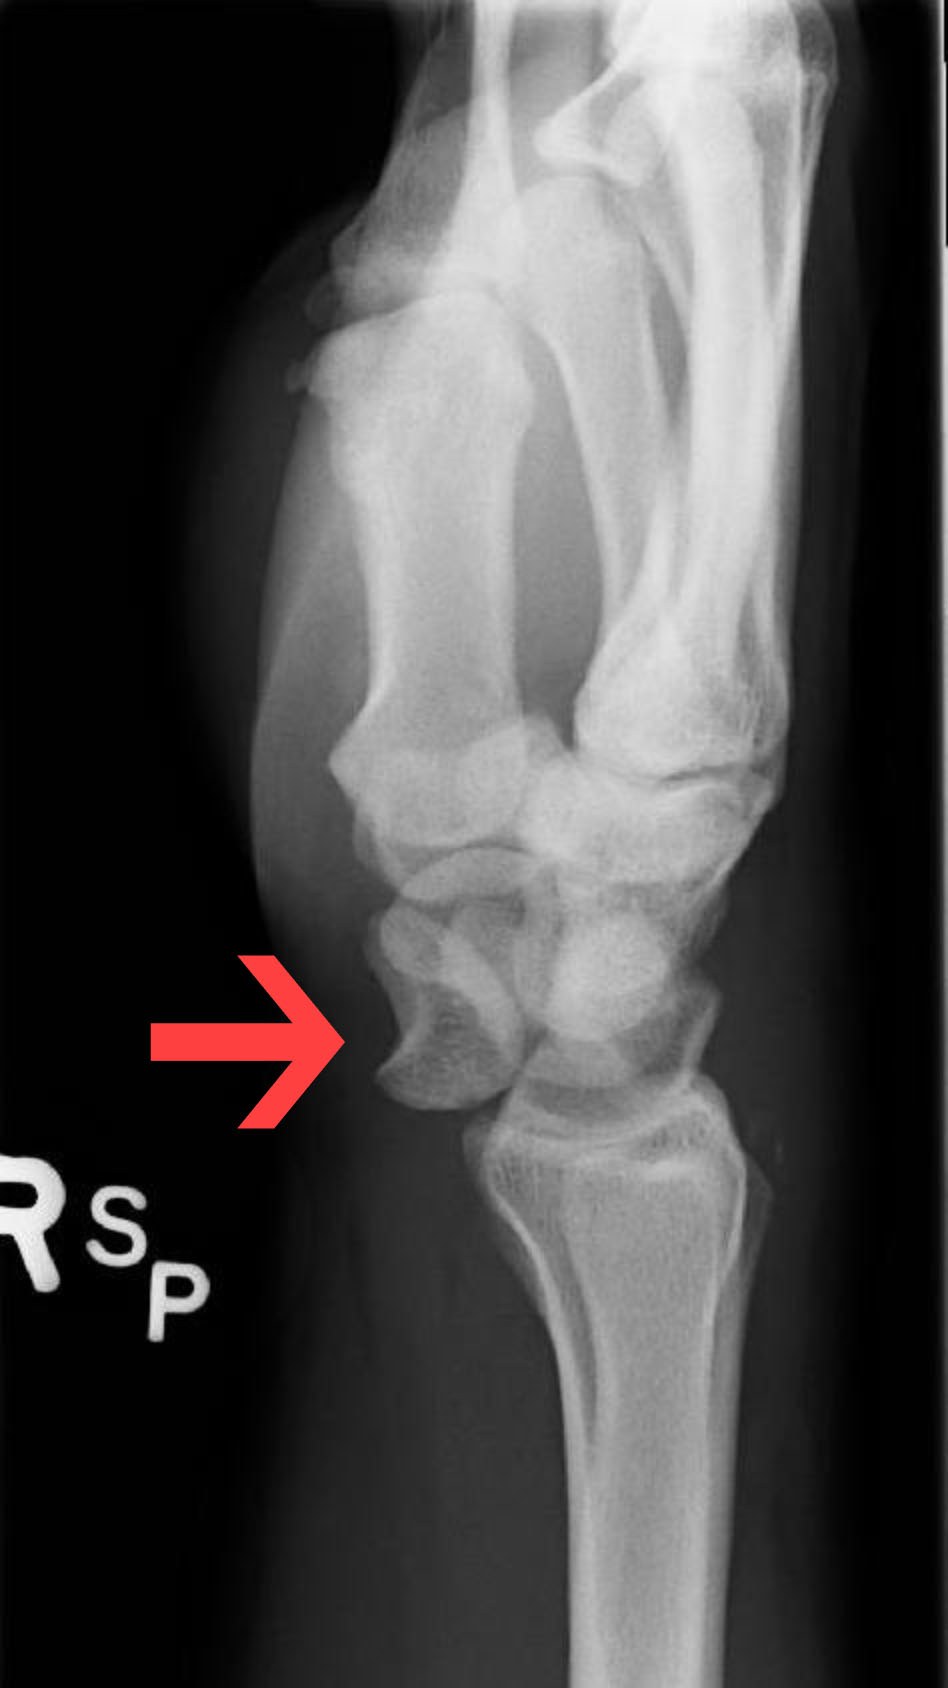

Because of the high energy associated with these injuries, perilunate dislocations, lunate dislocations, and perilunate fracture-dislocations account for less than 10% of all wrist injuries.25 High force applied to a hyperextended wrist in situations such as falls from heights on an outstretched hand or motor vehicle collisions can destabilize the surrounding structure through fractures and disruptions in articulations or ligaments, which may cause a perilunate dislocation, lunate dislocation, and/or perilunate fracture-dislocation. (See Figure 4.) The mechanism typically is wrist hyperextension, ulnar deviation, and intercarpal supination. In the case of perilunate dislocation, the lunate maintains its articulated position with the distal radius while the surrounding carpal bones dislocate dorsally. The most common symptoms are pain, swelling, and deformity. Loss of grip strength can occur, as well as median nerve compression, leading to paresthesia or numbness in the median distribution.26,27 This typically is present with more instability than lunate dislocations because of the involvement of multiple carpal bones.

The Mayfield classification divides perilunate instability into four stages. In stage one, there is rotatory subluxation of the scaphoid, disrupting the scapholunate ligament. On AP X-ray, increased distance indicates scapholunate dissociation for more than 3 mm can be seen, known as the Terry-Thomas sign. Stage two involves the lunocapitate disruption, and the lunate can project through the space of Poirier, which is an area between the capitate and lunate that has poor ligamentous support. In this stage, the lunate remains within normal alignment with the distal radius, where the remaining carpal bones are dislocated. Scaphoid fractures are common and typically are present in up to 60% of cases of lunocapitate disruption. In stage three, the lunotriquetral interosseous ligament is disrupted. Triquetral fracture also can be seen with this stage of injury. In this stage, neither the lunate nor capitate is aligned with the distal radius. The lunate is dislocated in stage four, involving the dorsal radiolunate ligament. A tipped teacup appearance can be seen on X-ray. (See Figure 5.) Physicians can attempt closed reduction, but it often is unsuccessful because of the complexity.26,27 Open reduction and internal fixation (ORIF) is the gold standard in treatment for this type of injury and allows for repair of ligamentous and bony injuries.26,27

Figure 5. Lunate Dislocation with Spilled Teacup Sign |

![]() |

Source: James Heilman, MD. https://commons.wikimedia.org/wiki/File:LunatedislocationL.jpg |

Perilunate dislocations typically are caused by high-energy traumas, such as falls from heights or motor vehicle collisions. The mechanisms typically involve wrist hyperextension, ulnar deviation, and intercarpal supination. The force vector travels from radial to ulnar direction, causing instability and damage to the complex ligamentous structures of the wrist. The most common symptoms are pain, swelling, and deformity. Loss of grip strength can occur, as well as median nerve compression, leading to paresthesia or numbness in the median distribution.26,27 Perilunate dislocations typically present with more instability than lunate dislocations because of the involvement of multiple carpal bones. Hand radiography usually is sufficient for diagnosis; however, CT scanning can be useful in assessing the extent and surgical planning.27